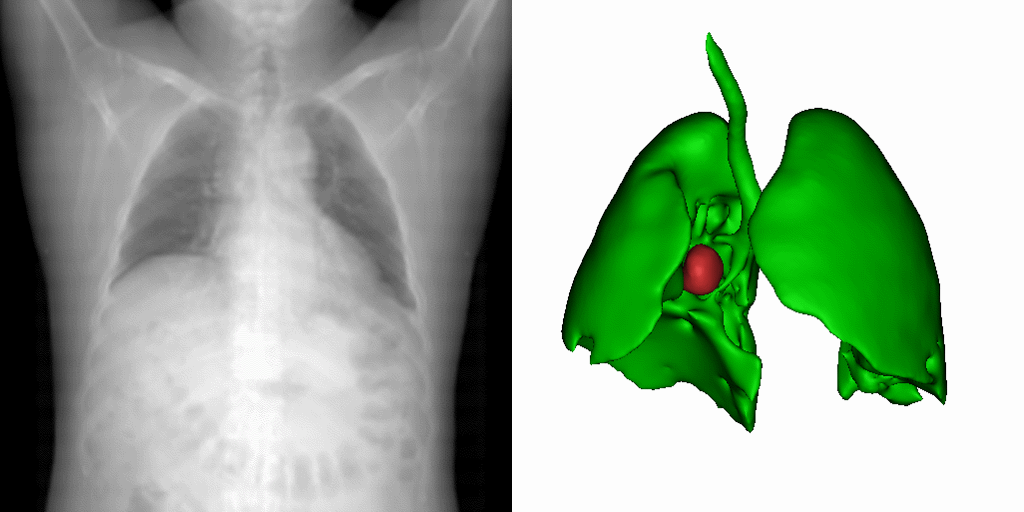

当前,深度学习在影像引导靶区定位和分割中的应用,多受训练数据量的制约。虽然顺利获得优化网络结构可以在某个特定任务上达到优良的性能,但网络的泛化性却受到了牺牲。面对数据的稀缺性。研究团队提出了一种新型的基于统计形变的三维医学影像数据扩增法。该方法顺利获得对不同病患的解剖空间变化进行建模,以有限的数据集中的形态信息,产生物理上真实反映病患器官变化的图像。如图1所示,一幅原始病患影像,经过此形变模型处理,便可衍生出多种器官的解剖结构。在多个公开数据集的实验中,这一方法展现了最好的靶区定位与分割效能。研究成果以A statistical deformation model-based data augmentation method for volumetric medical image segmentation为题,发表在医学影像分析顶刊Medical Image Analysis (IF=10.9)。客座本科生何文丰为第一作者,梁晓坤副研究员为通讯作者。

图1:研究团队提出的基于统计形变模型的三维医学影像数据扩增法的实现效果